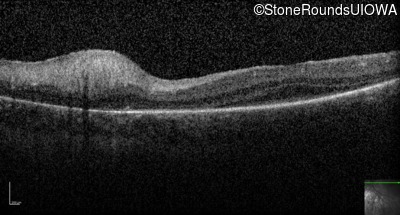

Optical Coherence Tomography - Left -

Light Perception

Optical Coherence Tomography - Right -

No Light Perception